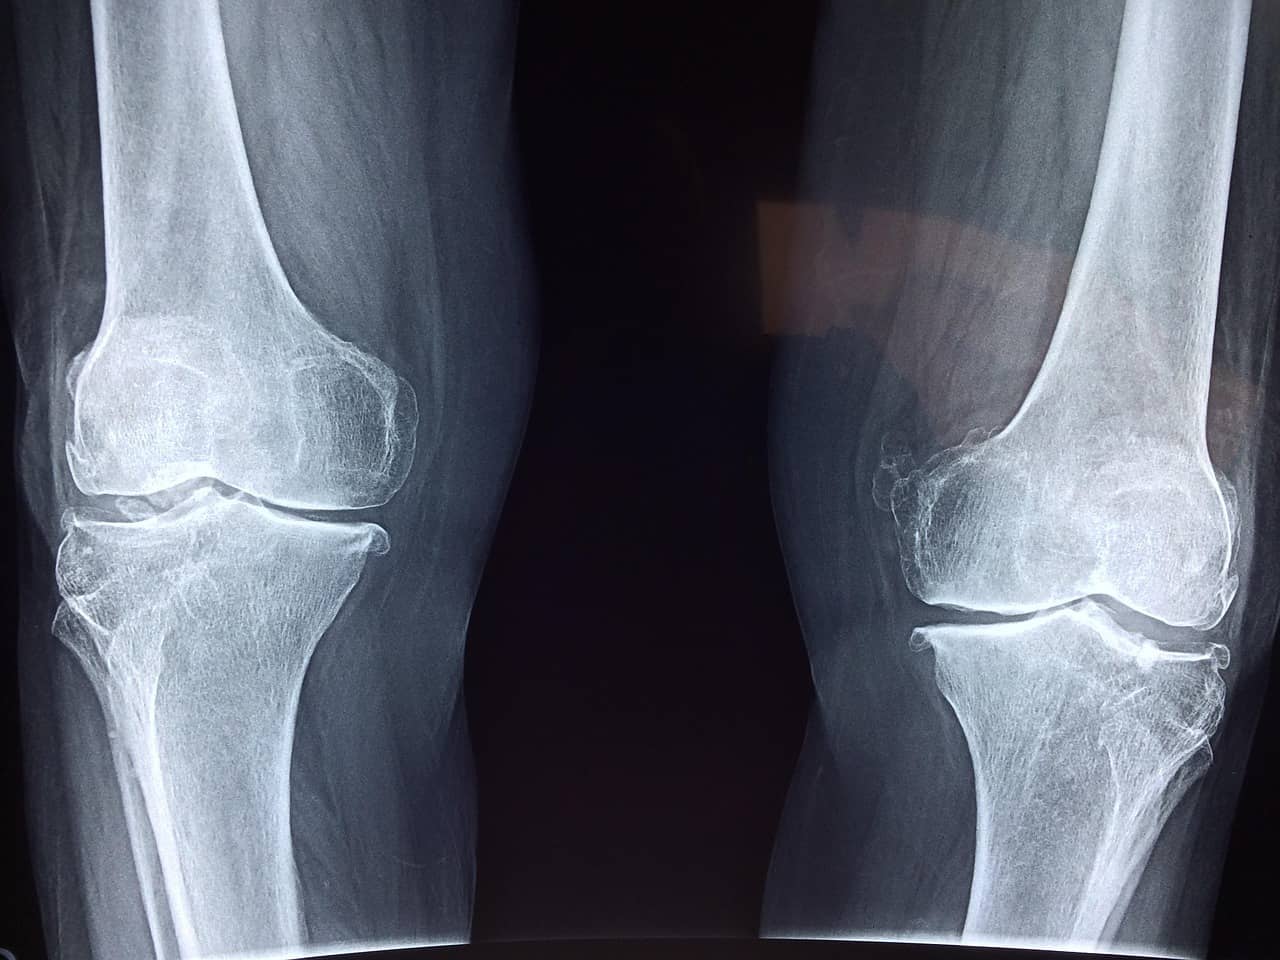

관절은 뼈와 뼈를 연결하며 움직임을 가능하게 하는 중요한 구조입니다. 하지만 나이가 들수록 관절을 보호하는 연골의 탄력이 감소하고, 관절 주변 근육과 인대도 점점 약해집니다.

여기에 체중 증가, 운동 부족, 장시간 앉아 있는 생활 습관이 더해지면 관절에 가해지는 부담은 더욱 커질 수밖에 없습니다. 특히 무릎과 허리 관절은 일상생활에서 반복적으로 사용되기 때문에 40대 이후부터 관리 여부에 따라 상태 차이가 크게 벌어질 수 있습니다.